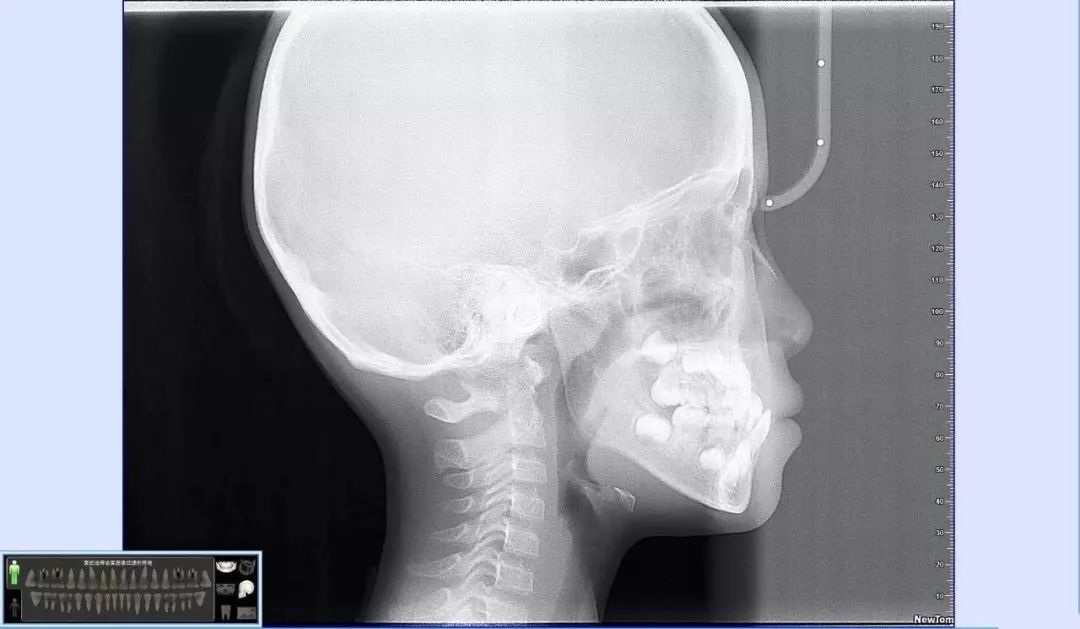

(2) 牙科头颅侧位片

牙科头颅侧位片

可以展现牙齿及颌骨影像。可见孩子侧面骨骼、上下颌骨发育 、气道、腺样体等各组织结构间是否影响孩子面型发育。

想要矫正牙齿的小朋友,以上两项牙片一定要拍哦~